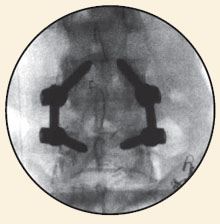

The nerve roots are then moved to one side and the disc material removed from the front (anterior) of the spine. A bone graft is then inserted into the disc space. The bone graft material acts as a bridge, or scaffold, on which new bone can grow. Screws and rods are inserted to stabilize the spine while the treated area heals and fusion occurs, and the ultimate goal of the procedure is to restore spinal stability.